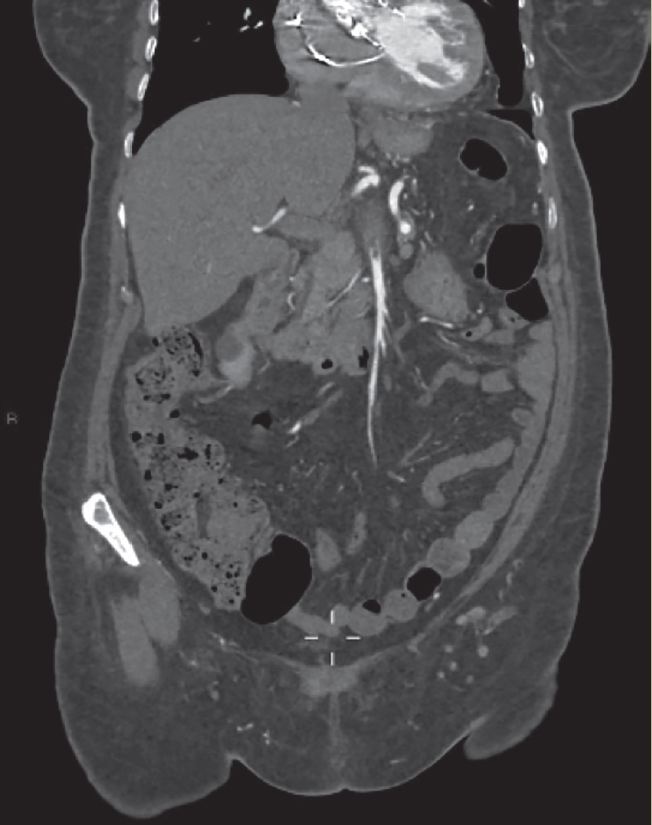

A su ingreso se solicitaron laboratorios generales, los cuales mostraron leucocitosis y anemia normocítica normocrómica grado I de la OMS, el resto de los estudios de laboratorio fueron reportados dentro de los parámetros establecidos por laboratorio; se decidió ingreso hospitalario para abordaje diagnóstico por anemia y gastropatía; se solicitaron estudios de laboratorio de extensión, los cuales reportaron sangre oculta en heces cualitativa positiva y examen general de orina con bacterias escasas. Se inició tratamiento con ceftriaxona y pantoprazol. Al persistir con intenso dolor abdominal, se solicitó tomografía abdominal simple, la cual sugirió trombosis mesentérica, por lo que se realizó complemento con angiotomografía abdominal, que reportó los siguientes resultados: trombosis segmentaria (figura 1) y en la totalidad de la luz de la arteria mesentérica superior con longitud de 37 mm, y posterior recanalización por vascularidad colateral (figura 2), trombosis de la iliaca externa derecha a 9 mm de su nacimiento, que se extiende hasta arteria femoral con opacificación distal (figura 3).

Figura 1 Angiotomografía abdominal, reconstrucción coronal en fase arterial, que muestra defecto de llenado en la arteria mesentérica superior en forma segmentaria y posterior recanalización.